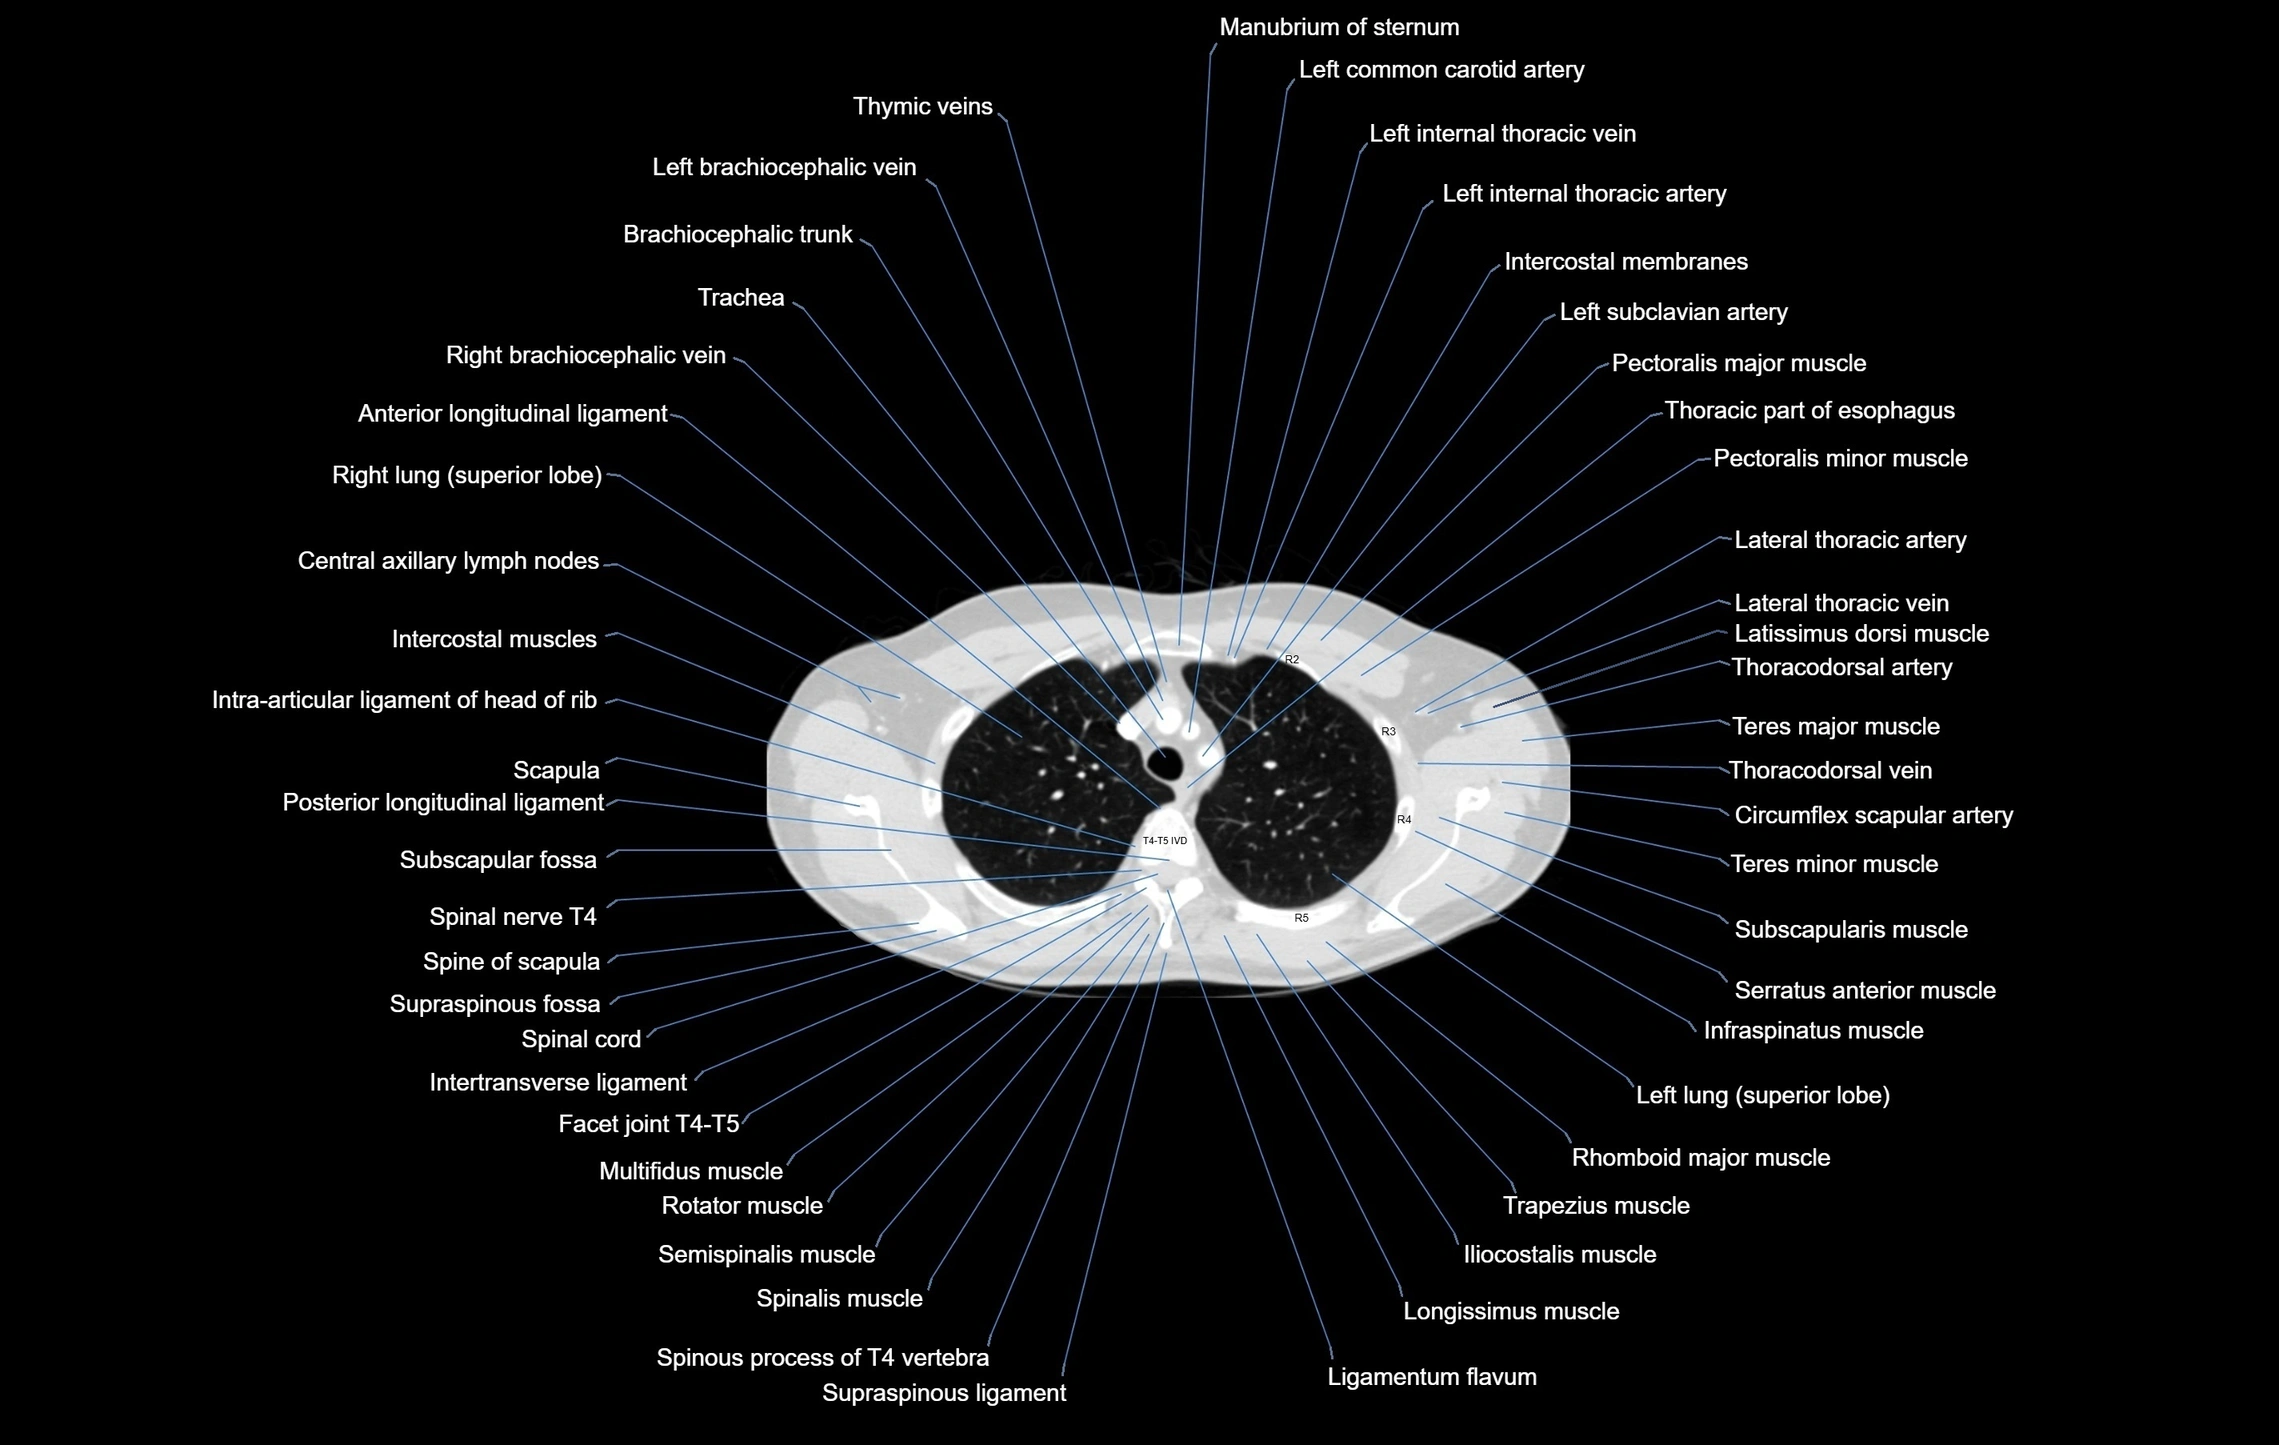

- T (Thoracic spine)